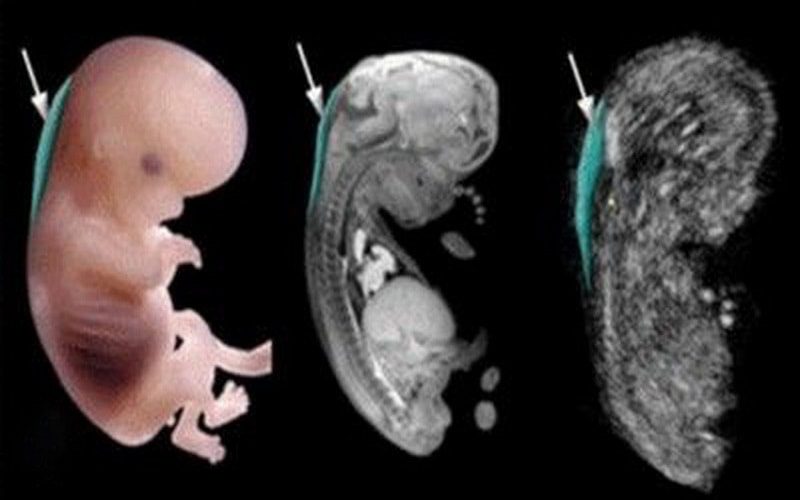

Dị tật ống thần kinh xảy ra khi ống thần kinh không đóng hoàn toàn trong giai đoạn đầu của thai kỳ, dẫn đến nứt đốt sống hoặc vô sọ.

3. Bất Thường Về Hình Thái Thai Nhi Qua Siêu Âm

Dấu hiệu:

+ Tăng khoảng sáng sau gáy

+ Dị tật về tim (thông liên thất, thông liên nhĩ…).

+ Dị tật ống thần kinh (nứt đốt sống, vô sọ…).

+ Dị tật chân tay, sứt môi, hở hàm ếch…

Tầm quan trọng: Việc siêu âm định kỳ giúp phát hiện sớm các bất thường về hình thái để can thiệp kịp thời.